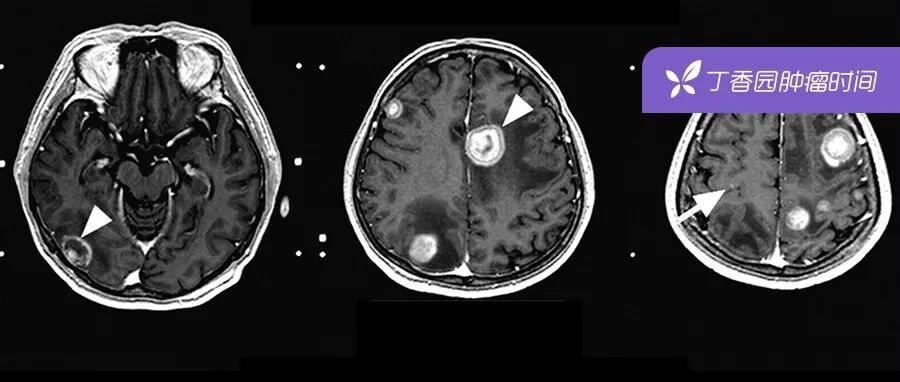

| 肺癌脑转移的 9 大治疗手段,最全总结都在这里! | 查看 | 2022-09-14 20:20:53 | 2799 | 6 | 2022-09-14 21:22:56 | 肿瘤时间 | |